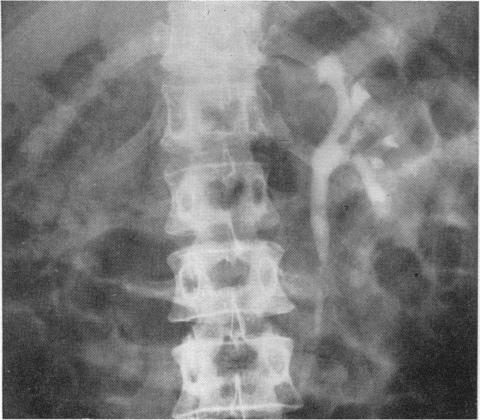

The diagnosis and treatment of renal-artery stenosis.

Br Med J. 1960 Jul 30;2(5195):327-38. doi: 10.1136/bmj.2.5195.327.